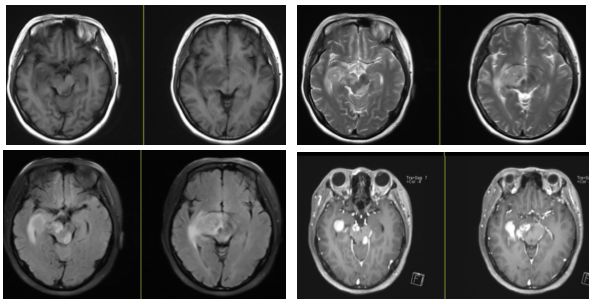

病例9(病例提供: 王浩玥 老师)

患者,女,55岁,因“突发视物重影1月,加重伴左侧眼睑下垂十余天”于入院,左侧上睑下,左眼向上、向下、向内活动受限,右眼各向眼动充分,伸舌右偏。

激素治疗半月后复查:

答案:间变性星形细胞瘤

好发于额叶、颞叶与顶叶的交界区,幕下少见。影像表现为浸润性肿块,主要累及白质。T1WI呈低信号,有出血时可见片状高信号区。T2WI呈高信号为主,常由于瘤内坏死而表现为混杂信号,DWI肿瘤实质部分呈稍高信号,坏死区呈低信号。瘤周水肿带呈长T1、长T2信号。通常不强化,少见局灶、结节样、均匀、斑片状强化。肿瘤组织可以通过细胞外间隙和沿白质束扩散,也可通过脑脊液和室管膜扩散,在播散通路上出现相似信号的肿块影。肿瘤内部不规整的线条状影指向周围脑实质,为本病较特征性的影像特点。